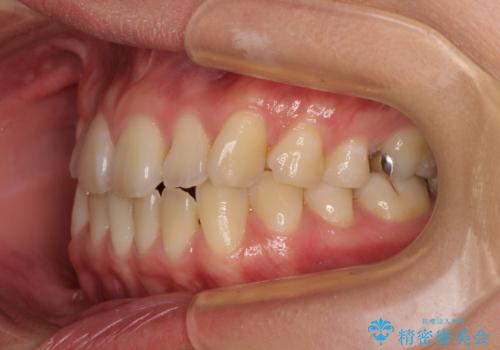

上下前歯のデコボコを気にして来院された患者様です。

ワイヤー矯正でもマウスピース矯正でも可能でしたが、短期間で、自身の手を煩わせることなく治療を行いたいとのことで、ワイヤー装置にて矯正治療を行うこととしました。

舌の突出癖により、治療過程でスペースが多くできましたが、舌のトレーニングを頑張っていただき、1年強で終えることができました。